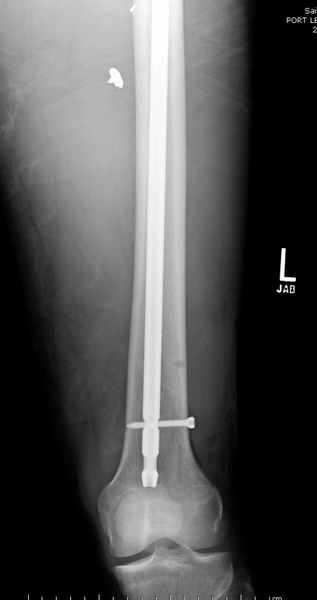

Учитывая, что больной получил травму не во время визита в церковь, и он является одним из представителем 40 миллионного “outstanding itizen”, без медицинской страховки, без работы в свои 39 лет, и без надлежающей ортопедической дисциплины у которого отсутсвует страх стрессового перелома, было рекомендовано оперативное лечение: профилактическое антеградное интрамедуллярное штифтование.

Методика штифтования при отсутствии большой зоны перелома как при онкологических профилактических штифтованиях, расверливание интрамедуллярного канала проводим с предварительным наложением дополнительного дренажного отверстия в дистальном отделе бедра (в данном случаи в канале оставили 6.5 мм канюлированный шуруп), иначе при создании давления в канале во время сверления имеется опасность эмболизации легочной артерии тромбом.